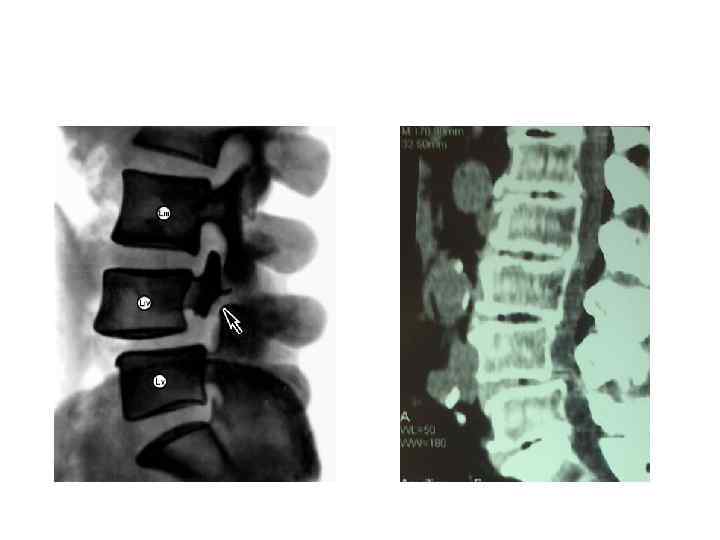

Переломы тел позвонков

Переломы тел позвонков